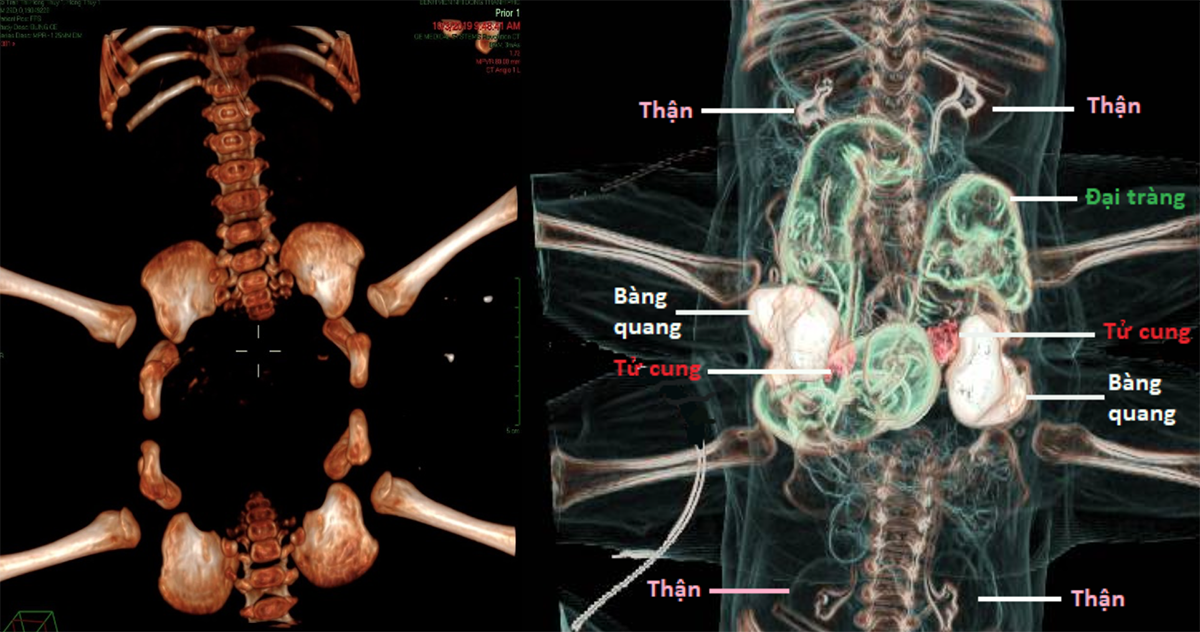

Với các phương tiện chẩn đoán hiện đại dành cho Nhi khoa như chụp cộng hưởng từ (MRI), Chụp vi tính cắt lớp mạch máu (CTA) các bác sĩ chẩn đoán hình ảnh của bệnh viện đã phát hiện hàng loạt các bất thường tại vùng bụng chung. Về hệ tiêu hóa: 2 bé có chung 1 phần hồi tràng, 1 khung đại tràng và chỉ có 1 lỗ hậu môn. Về hệ thận niệu: 2 bé có 2 bàng quang nằm 2 bên của ổ bụng chung, mỗi bàng quang được 2 niệu quản xuất phát từ 2 bé khác nhau đổ vào thay vì của cùng 1 bé. Về cơ quan sinh dục 2 bé có tử cung âm đạo đôi. Ngoài ra, 2 bé còn có hở khớp mu, khung chậu 2 bé lại xếp thành 1 vòng tròn.